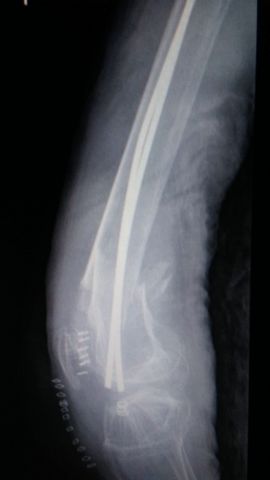

Fractura de fémur, osteosíntesis

Fractura de húmero, intensa desviación de fragmentos

Fractura de húmero.

Fractura compleja de húmero.

Fractura de diáfisis de húmero.

Fractura de húmero tras osteosíntesis con clavo gamma.